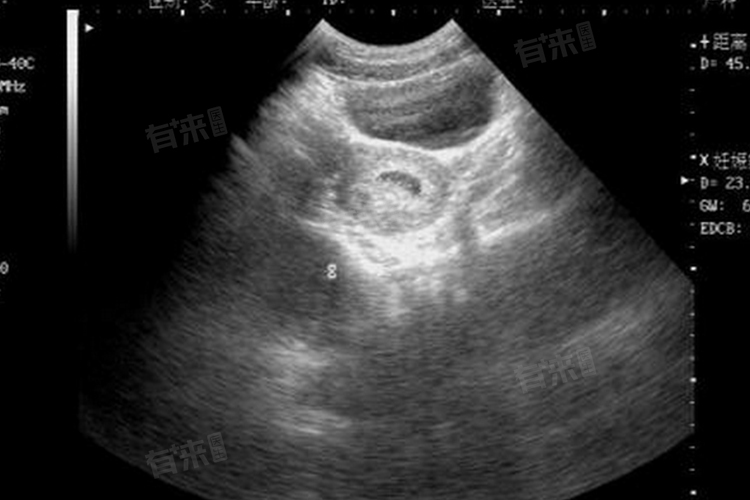

- 如果在怀孕五周时进行经阴道超声检查看到了孕囊,通常孕囊的大小会比较小,可能只有几毫米。此时,孕囊可能呈现为一个圆形或椭圆形的无回声区,位于子宫腔内。